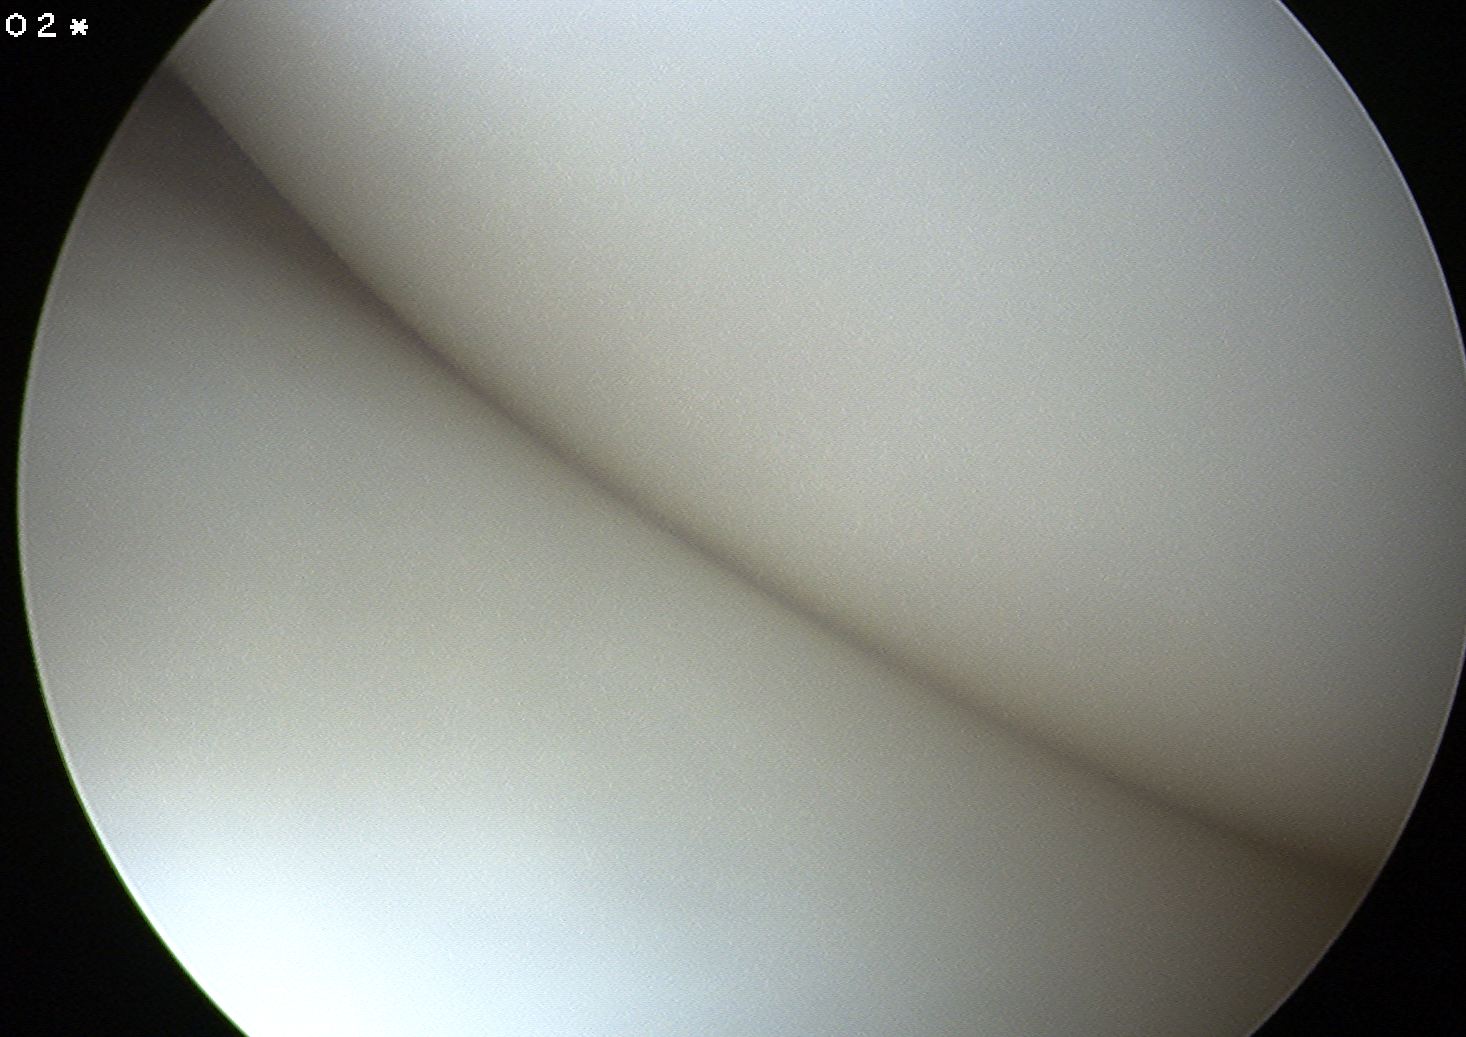

Classification Watanabe

1. Complete

- entire articular surface of tibial plateau covered by thickened abnormal meniscus

- minimal symptoms

- stable - i.e. capsular attachments intact

2. Incomplete

Normal peripheral attachments but not as extensive as complete type